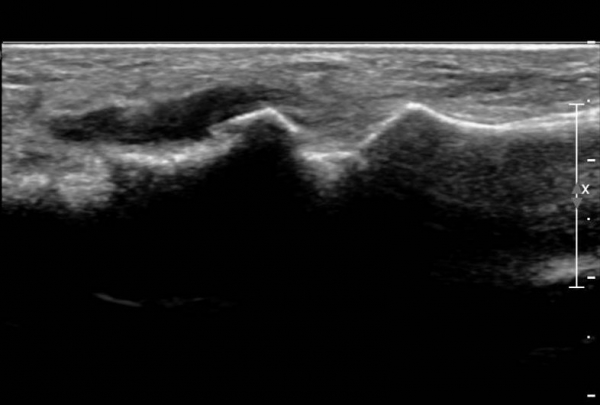

ŽÃËÀÚ¸¦ ¾à°£ ¹ß¹Ù´ÚÃøÀ¸·Î À̵¿ÇÏ´Ï ¼³Çü°ñ ºÎÂøºÎ°ÇÀÇ Àú¿¡ÄÚ º´º¯ÀÌ ¶Ñ·ÈÇÏ´Ù(»çÁø 3, 4).

Àü°æ°ñ°Ç Ⱦ´Ü¸é°Ë»ç¿¡¼­ Á»´õ ¹ß µîÃøÀ¸·Î À§Ä¡ÇÏ´Â Á¦1ÁßÁ·°ñºÎÂøºÎ °ÇÀº °í¿¡ÄÚ·Î Á¤»óÀûÀÎ ¾ç»óÀ¸·Î

°üÂûµÇ³ª Á»´õ ³»Ãø ¹Ù´ÚÃø¿¡ À§Ä¡ÇÏ´Â ¼³Çü°ñ ºÎÂøºÎ °ÇÀÇ Àú¿¡ÄÚ º´º¯ÀÌ °üÂûµÈ´Ù(»çÁø 5,  6).